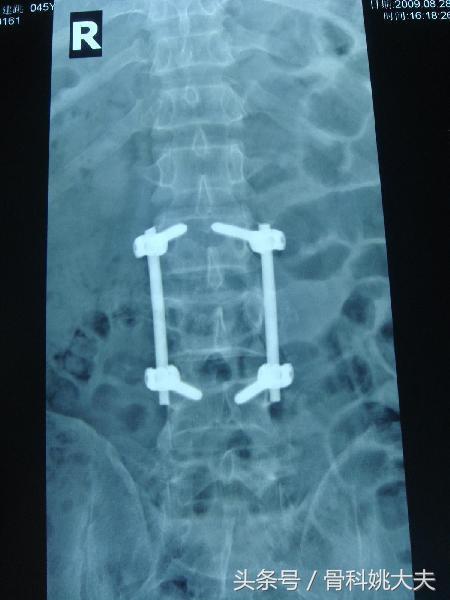

首先,腰部骨折手术做完之后,至少需要卧床休养三个月,在这三个月期间尽量不要下床,不要坐,只是卧床休养。这样可以避免腰部骨折处再次发生损伤,久坐会给腰椎部分形成压力,不利于骨折处的愈合。